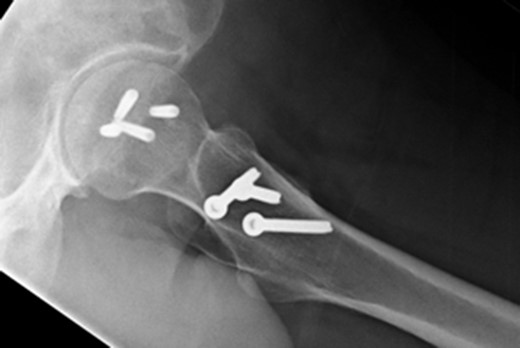

At 14 months postoperative, the patient is pleased with his progress. There is no radiographic evidence of avascular necrosis at this stage (Figs 6 and 7). He regularly participates in activities such as cycling, and scores well on the modified Harris Hip Score (81/100), non-arthritic hip score (92.5/100) and SF-12 (41/48).